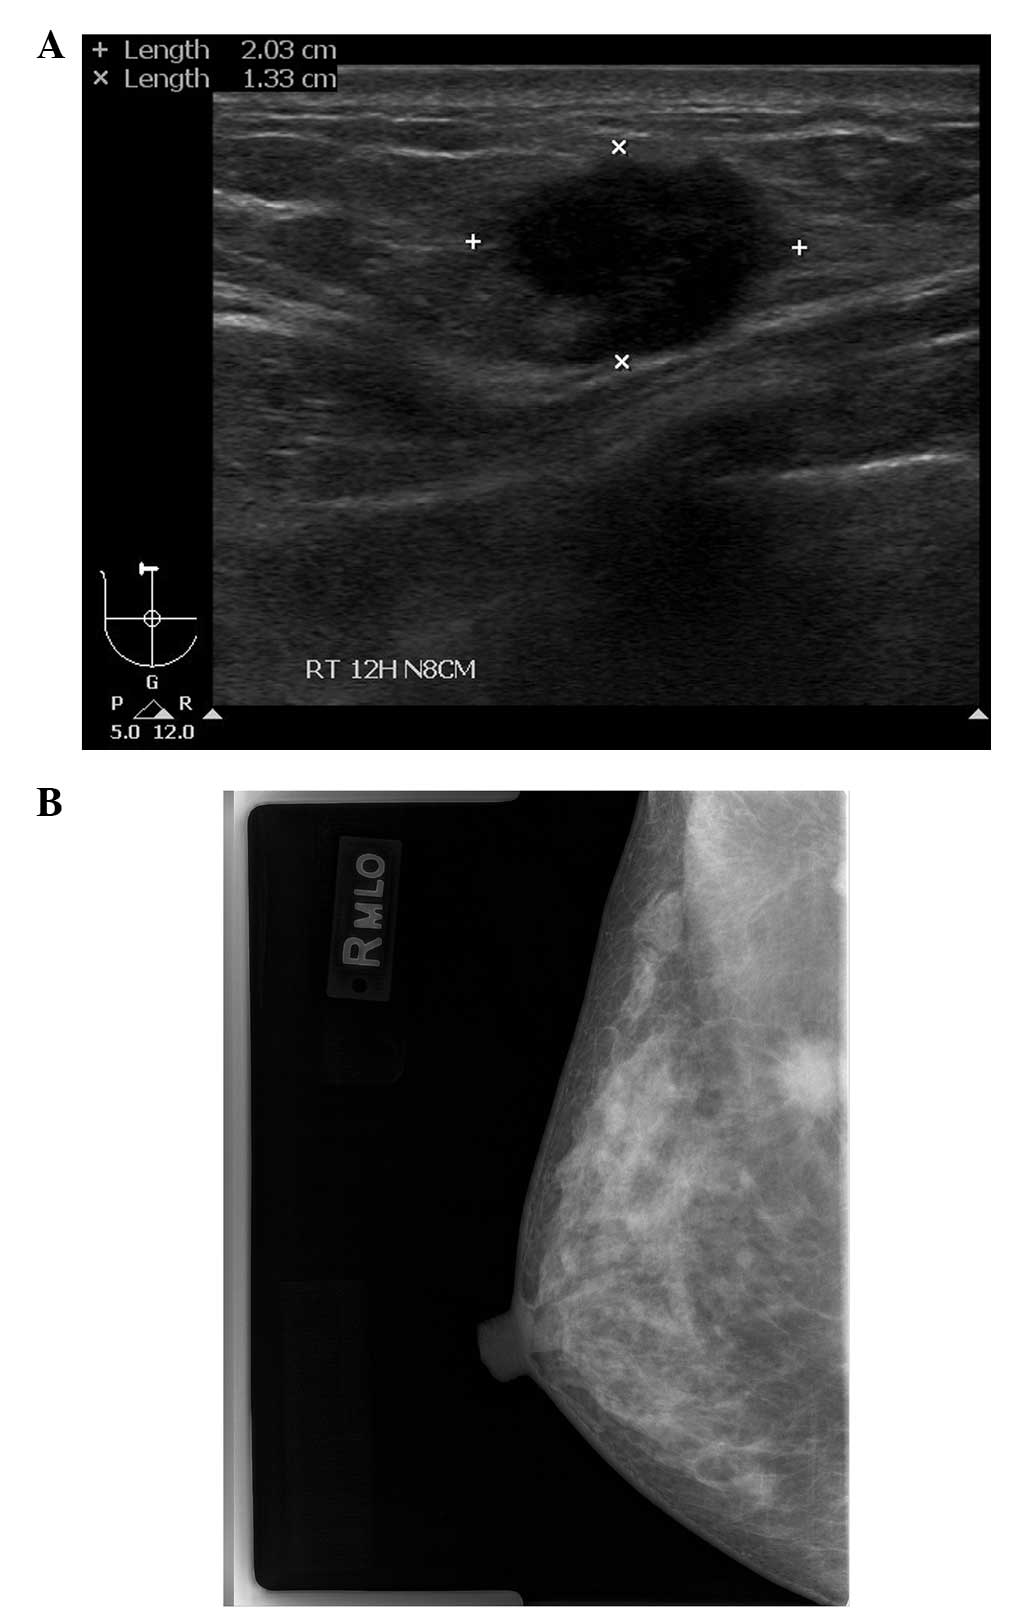

Physical examination and imaging

Upon physical examination, a fixed, firm mass, 2 cm in diameter, was palpated without tenderness in the right breast. There was no clinical evidence of regional lymphadenopathy. Mammography revealed a spiculate hyperdense lesion in the upper portion of the right breast (Fig. 1A). Ultrasonography (USG) revealed an irregularly-shaped hypoechoic lesion in the right breast in accordance with the finding of the mammography (Fig. 1B). The patient underwent an ultrasound-guided core needle biopsy, which revealed the features of an invasive ductal carcinoma. Radiological studies, including computed tomography (CT) of the chest, magnetic resonance imaging (MRI) of the breast and positron emission tomography-CT (PET-CT) of the torso were conducted for pre-operative evaluation of the right breast cancer. PET-CT showed metabolically active lesions in the right breast, the anterior mediastinum, the peripancreatic area of the upper abdomen and the left adrenal gland, which corresponded to the lesions observed on the CT scan (Fig. 2). In addition, the left thyroid gland and the endometrium of the uterus showed mild FDG uptake on the PET-CT, and a suspicious metastatic nodule of the lung was observed on the CT scan. The findings of an additional abdominopelvic CT scan indicated a neuroendocrine tumor of the pancreas, paraganglioma, a left adrenal adenoma, gallstones and uterine subserosal myoma.

Figure 1

Radiological findings of the right breast. (A) Mammography showing a spiculate hyperdense lesion in the upper portion of the right breast. (B) Ultrasonography (USG) scan showing an irregularly-shaped hypoechoic lesion in the right breast.